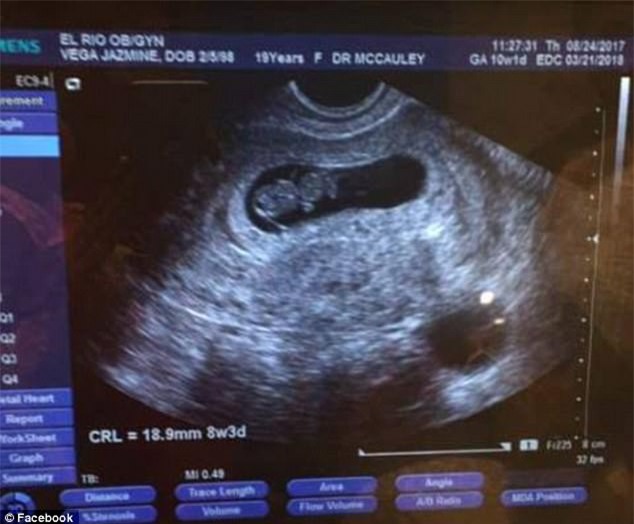

Một số người hàng xóm cho biết, vào khoảng 4h30 sáng, họ nghe thấy một tiếng thét thất thanh phát ra từ ngôi nhà ở miền Nam Arizona (Mỹ) và sau đó im bặt. Cảm thấy điềm không lành, họ đã nhanh chóng gọi cho cảnh sát và khi đến nơi, cảnh sát phát hiện Jasmine đã vô thức và chuyển đến bệnh viện địa phương nhưng các bác sĩ tuyên bố cô đã qua đời. Theo báo cáo, tại thời điểm Jasmine bị bắn chết, cô đang mang thai 6 tháng.

Thai nhi 6 tháng đã được các bác sĩ cứu sống ngoạn mục. (Ảnh: Internet)

Đại diện cảnh sát Tuscon, Arizona cho biết: “Sau khi chúng tôi phát hiện nạn nhân là một thai phụ. Đã nhanh chóng chuyển cô ấy đến bệnh viện và tiến hành cứu đứa bé. Hiện tại, đứa bé đang điều trị tại bệnh viện”. Cha của đứa bé, anh Anthony Rivera nói với Tuscon News rằng con anh đang trong tình trạng nguy kịch và cần sự hỗ trợ của các y bác sĩ.